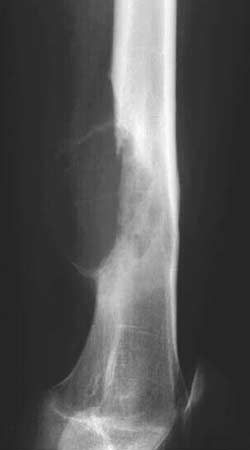

Рис. 3. Аневризматическая костная киста бедренной кости. (Слева) Рентгенограмма в боковой проекции. (Справа) Компьютерная томограмма.